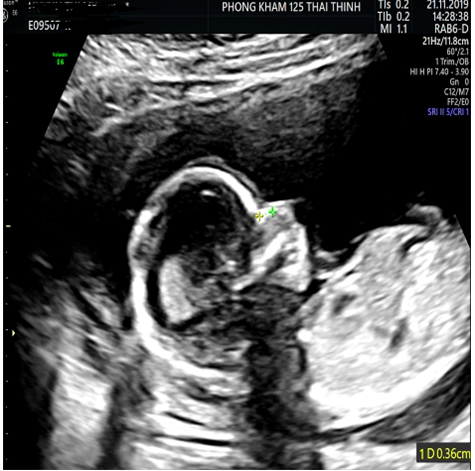

Giai đoạn 1: Đo trong Quý I (tuần 12) của thai kỳ

- Trong giai đoạn này, bác sĩ chỉ đánh giá thai nhi có xương mũi hay không và chưa quan tâm đến chiều dài xương mũi. Nếu thai nhi không có xương mũi thì thai nhi được xếp vào nhóm nguy cơ cao mắc bệnh Down.

- Nhưng mẹ cũng không cần quá lo lắng, vì giai đoạn này vẫn còn khá sớm để kết luận tình trạng của trẻ, thay vào đó mẹ nên theo dõi và kiểm tra lại sau 1-2 tuần (Giai đoạn 2). Cùng với đó các mẹ cần làm thêm các xét nghiệm sàng lọc như Double test hoặc xét nghiệm sàng lọc có giá trị cao như sàng lọc không xâm lấn NIPT.

| 11- 12 | 1. 5 - 2.4mm | Giai đoạn bắt đầu có thể đo xương mũi rõ ràng |